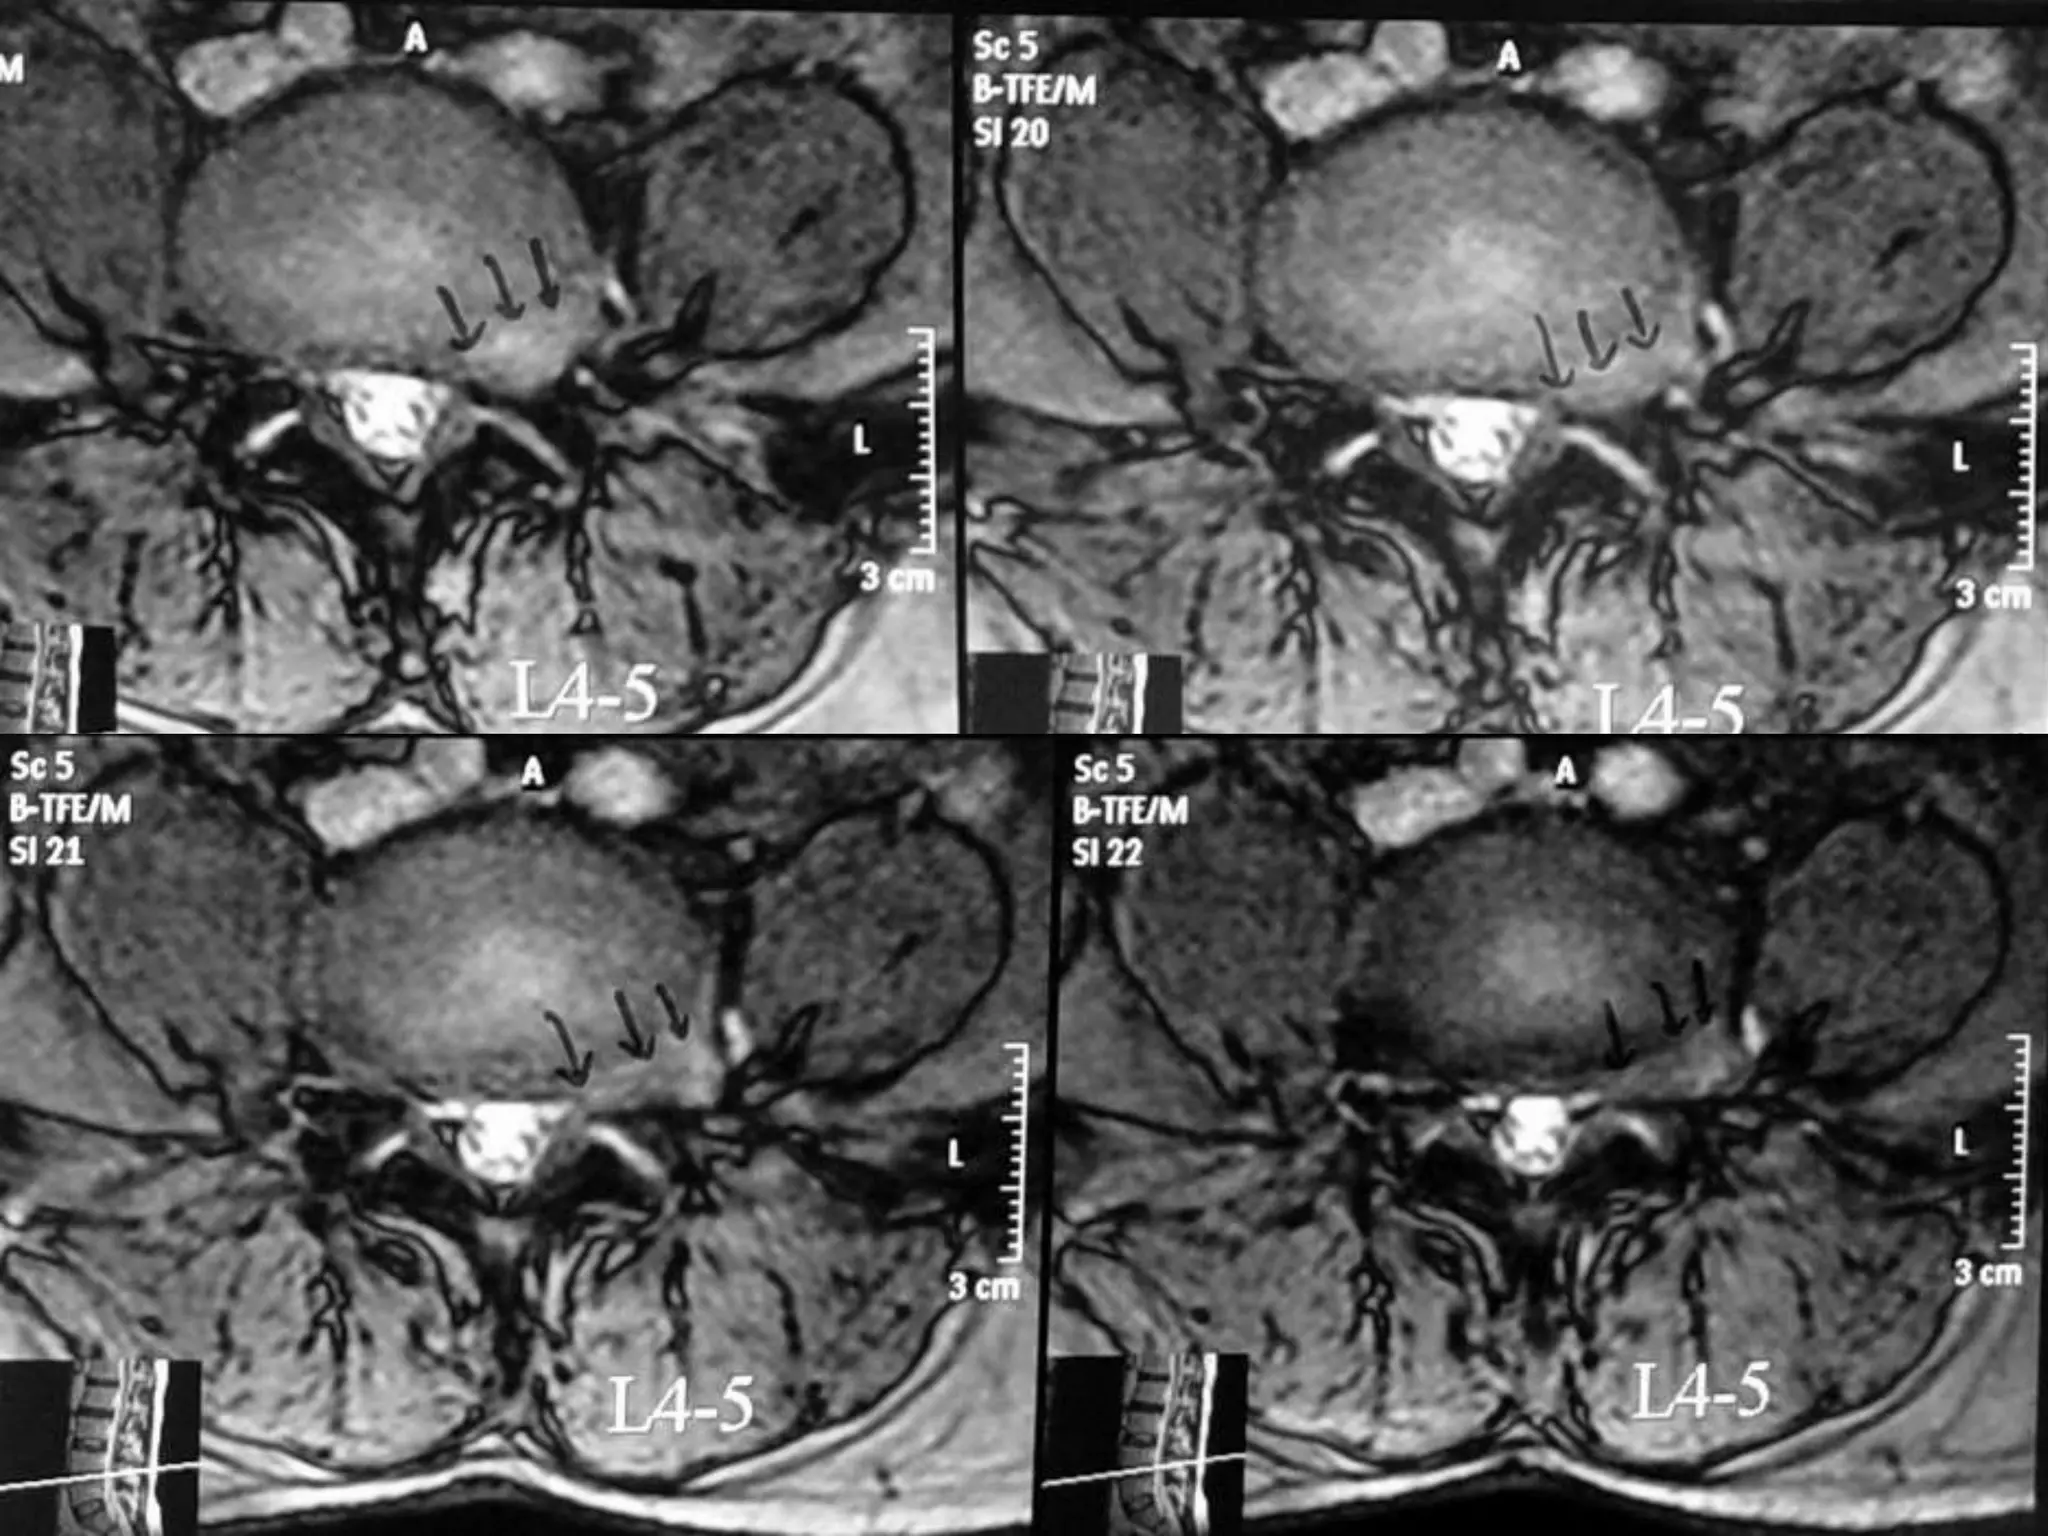

Far Lateral Disc Prolapse